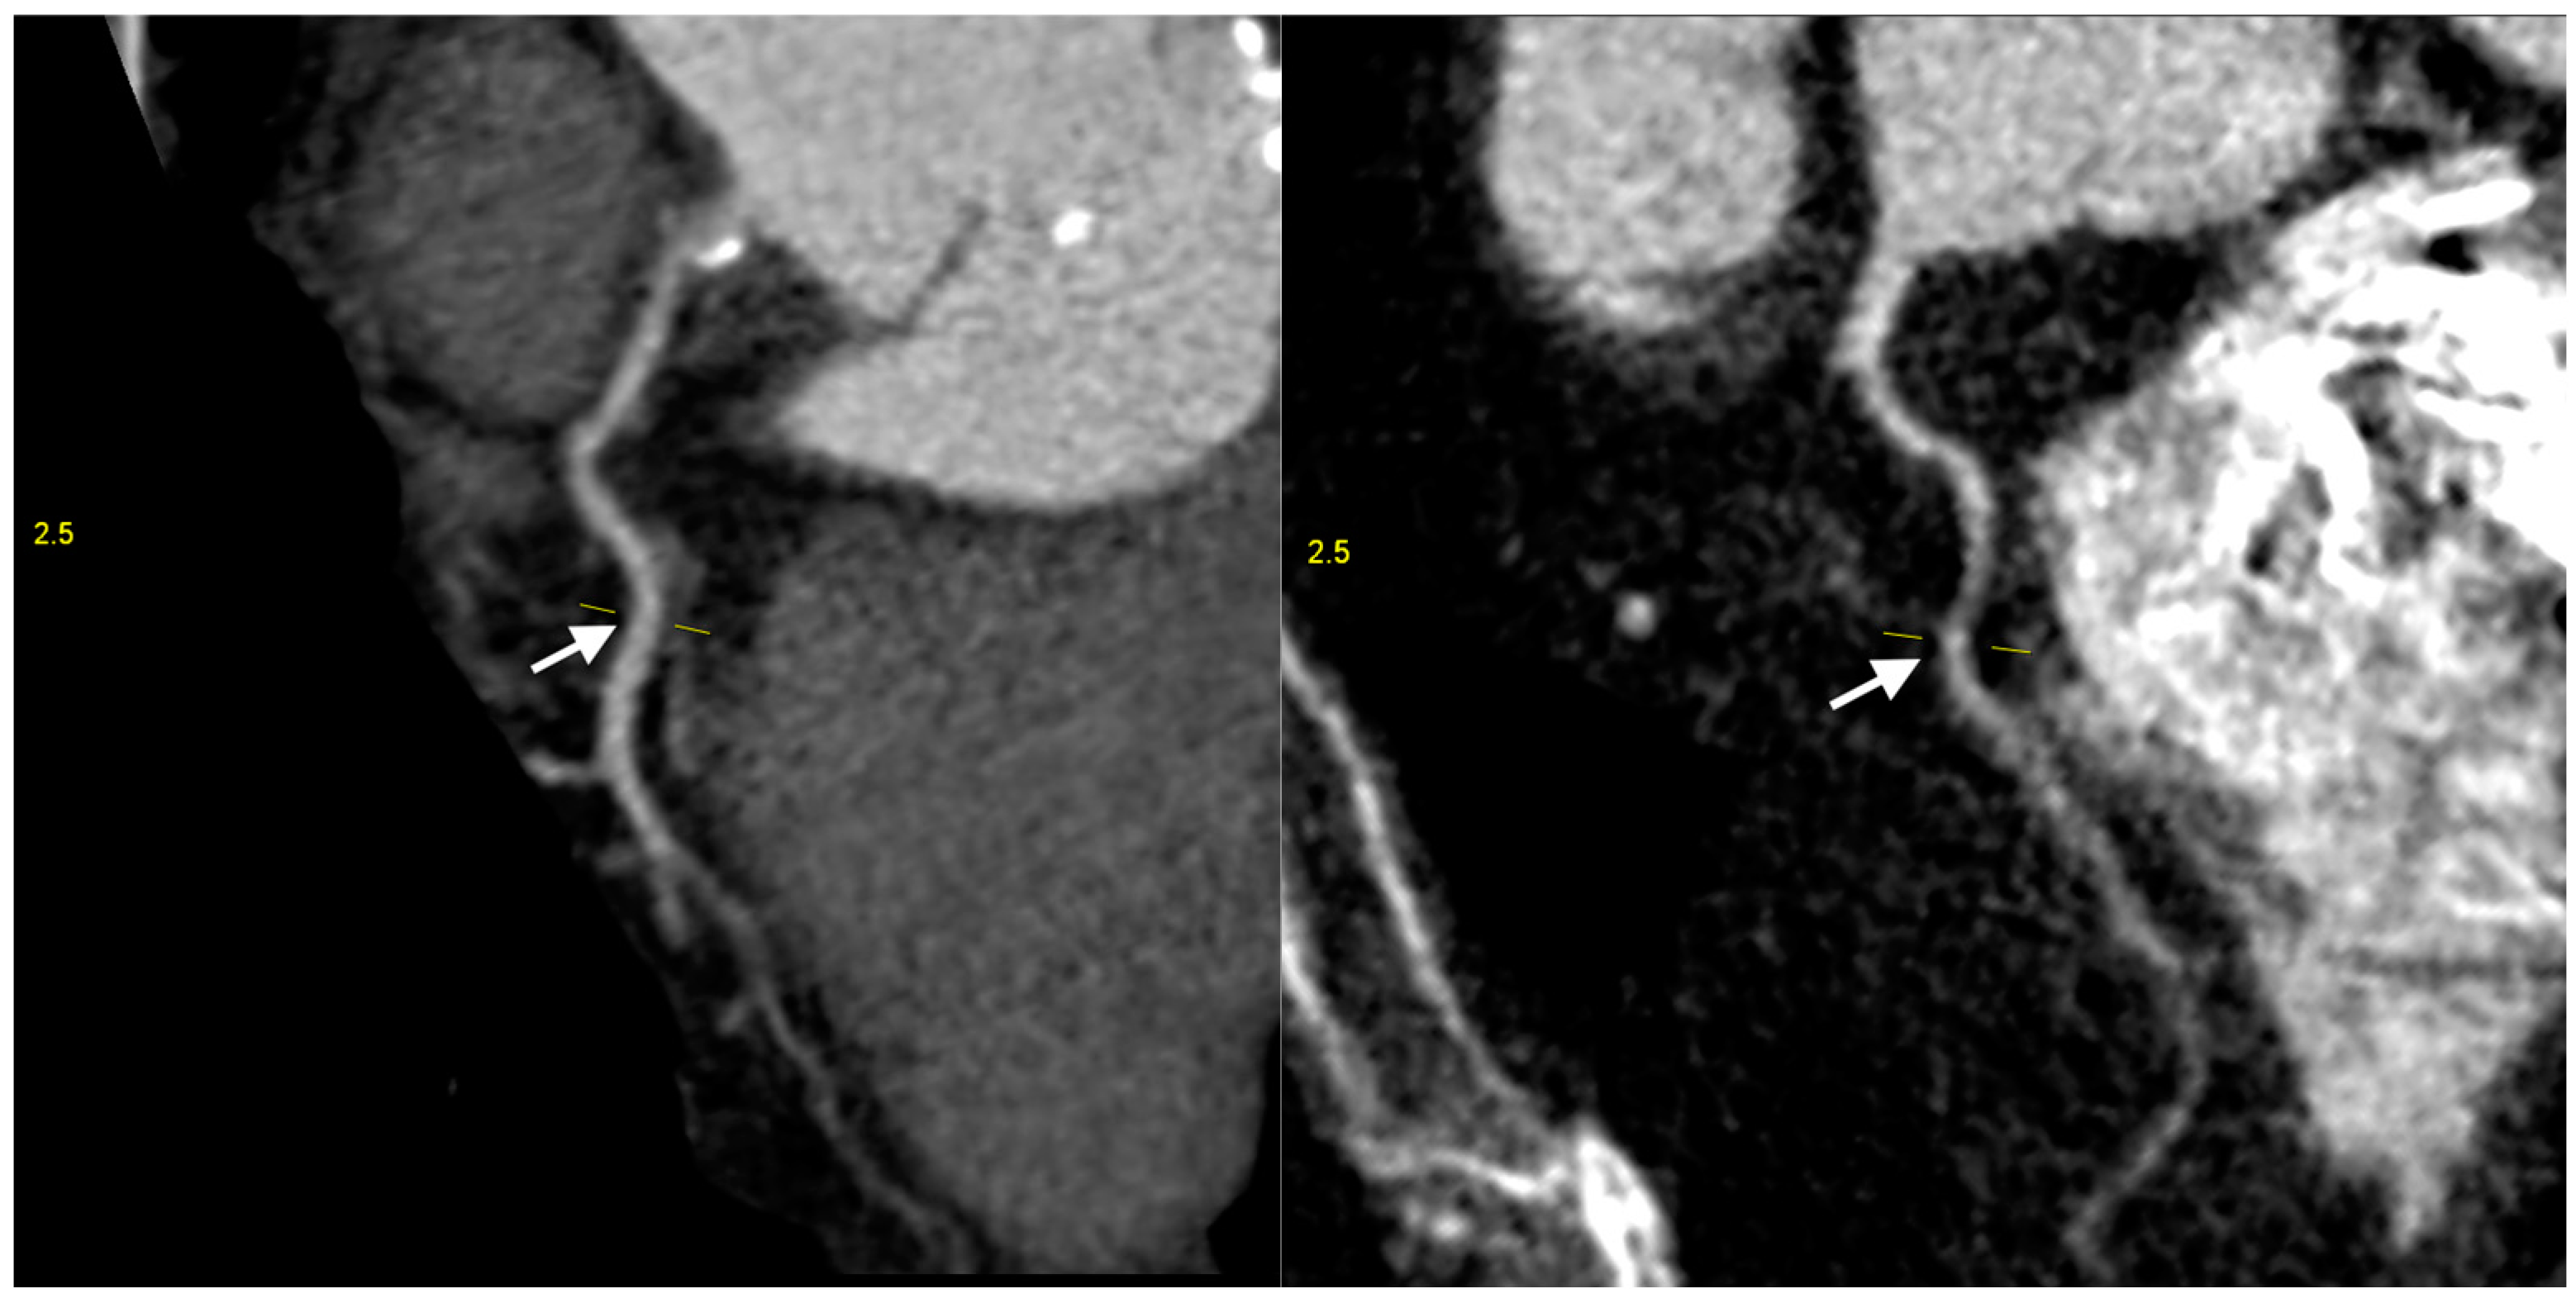

| Coronary artery hypoplasia | 71 | 20.3% | 0.5% |